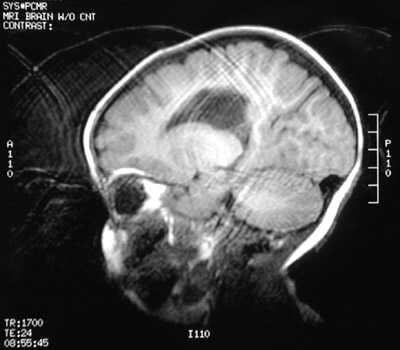

| The cerebrum to the right of midline in a case of "cerebral palsy" is seen here in a sagittal MRI scan. The mild loss of white matter, basal ganglia, and thalamus on the right led to ex vacuo ventricular dilation. (Note the artefact with shadowing due to motion--it is hard to keep an infant still for an MRI). Physical therapy helped to improve this infant's condition. |